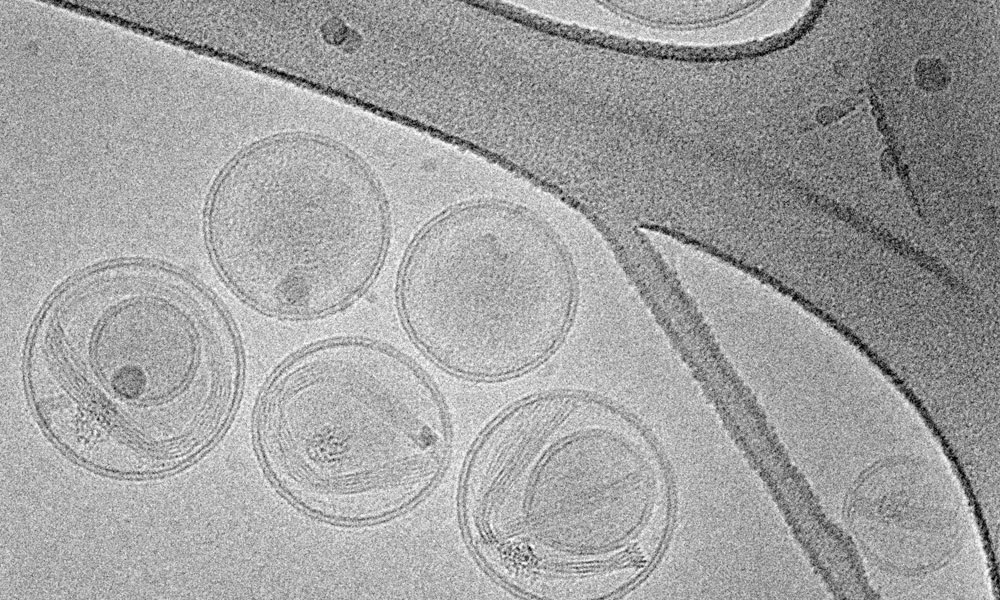

Esta configuración experimental duró siete días. Después de un período de 35 días, se extrajeron tejidos de sangre, hígado y riñón para la evaluación de varios parámetros, como la superóxido dismutasa (SOD), la catalasa, la capacidad antioxidante total (TAC), el malondialdehído y la creatinina tisular.